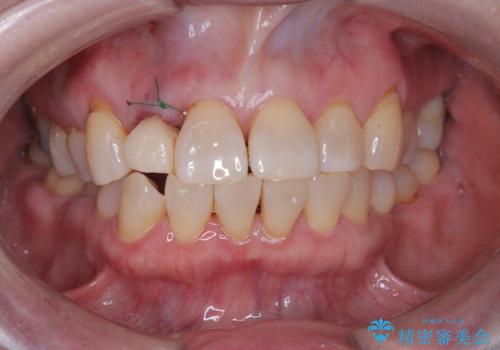

そのため今回は、右上2番を抜歯し、右上1番および左上1番をオールセラミッククラウンで審美的に修復しました。

また、歯科治療への不安が強かったため、静脈内鎮静法を併用してリラックスした状態で治療を行いました。

治療期間も短く、抜歯からわずか3か月でオールセラミッククラウンを装着することができます。

また、オペ当日には仮歯まで装着するため、見た目を気にせず普段通りの生活を送ることができます。